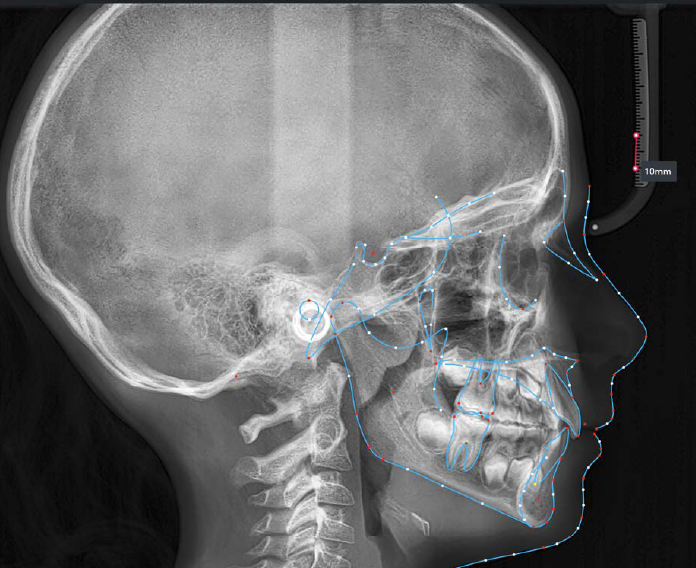

The patient presented with a skeletal Class I relationship and a mesofacial growth pattern, indicating balanced sagittal and vertical skeletal proportions. Dental examination revealed a Class I molar and canine relationship bilaterally. The patient was in the mixed dentition phase. Significant dental crowding was observed in both arches, consistent with a dentoalveolar discrepancy. Midline deviations were present, affecting dental symmetry and occlusal harmony. The maxillary lateral incisors were in crossbite, contributing to anterior transverse discrepancy and functional imbalance.

The orthodontic treatment plan was designed to address dentoalveolar crowding, transverse discrepancies, and midline deviations, while maintaining optimal periodontal health and achieving stable Class I molar and canine relationships. Specific objectives included correction of anterior crossbite, expansion and coordination of the arches, derotation of upper molars, preservation of incisor inclinations, derotation of lower posterior teeth with lingual root torque, leveling of the curve of Spee through incisor intrusion and controlled extrusion of deciduous teeth, and normalization of incisor inclinations. A clear aligner–based approach was selected to allow precise, controlled tooth movement, with particular

attention to root parallelism in the anterior region. The treatment was carried out in two phases: an initial phase of 20 aligners focused on primary alignment, space redistribution, and preliminary correction of malocclusion, followed by a refinement phase of 10 aligners aimed at finalizing tooth positioning, improving intercuspation, optimizing overbite and overjet, and enhancing overall occlusal stability. The refinement phase was considered an integral component of the treatment strategy and is explicitly highlighted to emphasize its role in achieving optimal finishing and long-term functional and aesthetic outcomes.